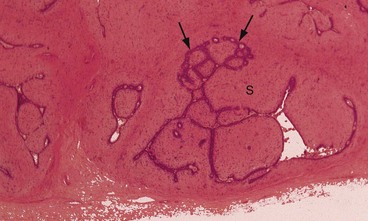

Tumour types: Almost all breast cancers are adenocarcinomas and arise from the terminal duct/lobular unit. Over 85% originate from the ductal component and are designated invasive ductal carcinomas of ‘no special type’ (NST) (Fig. 45.9). About 8% arise from the lobules and are known as lobular carcinomas. These are similar in behaviour and prognosis to ductal carcinomas but can be difficult to see on mammography and often present late. Microscopically these tumours are characterised by linear arrangements of cells, so-called ‘Indian filing’ (Fig. 45.9b). A few invasive carcinomas have ductal and lobular features and are termed ‘mixed’ tumours.

Fig. 45.9 Breast adenocarcinoma—histopathology

(a) Ducts to the left of the picture contain highly atypical epithelium, with central necrosis N, a type of in situ ductal carcinoma also known as comedocarcinoma. On the right of this micrograph is invasive ductal carcinoma composed of many small glandular structures diffusely invading breast tissue. (b) In situ IS and invasive lobular carcinoma. Malignant cells tend to be less atypical than in ductal carcinoma and do not form glands, but often invade in ‘single-file’ (arrowed). Intracellular mucin is also characteristic of this variant of breast carcinoma